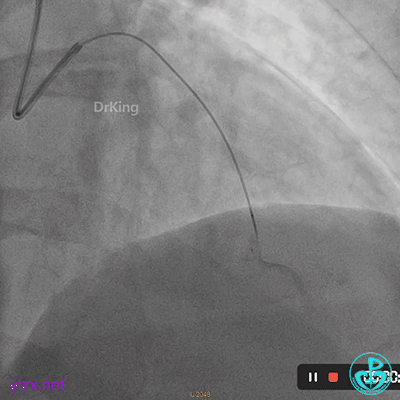

07 2个月后再次造影

处理前降支病变,导丝Pilot 50通过LAD病变到达远段,沿导丝送入穿通导管至远段,回抽有血,造影提示在真腔。

PTCA球囊扩张后无前向血流,以硝普钠反复行冠脉内局部药物释放治疗术。

复查造影提示LAD血流恢复TIMI血流2-级。